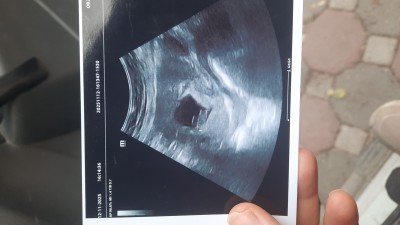

Kızlar biliyorum daha çok erken 2 oglum war.sizce bu ultrason görüntüsü hanginiz benziyor hangisi geçti içinizden daha 8 4 günlük

Ortada daha bebek yok, ne cinsiyeti 😂

Kızz 😁 ... Kızıma hamile iken bı tanıdık demişti kı kız kesesı yuvarlak erkek kesesı daha yaygın sekıllı oluyor demıstı oval  gıbı düşünün ... Şuan ıkıncıe hamileyim cinsiyetı de erkek. Ikı keseyı karşılastırmıstım doğru bana göre 😁

Sizde tecrübeli siniz aslında 2 çocuğunuz var benziyor mu diğer gebeliğe bende iki oğlum var kesesi fasulye gibiydi sizin kız de olabilir geçen gittim 3 cu bebeğim için yine fasulye gibi kese gördük eşim de acayip bu da erkek olursa ne istersen alırım ama ne istersen dedi enteresan:) ama benim için hiç farketmez

Canim walla 2 oğlumda ilk yuvarlaktı sonraki hafta fasulye gibi oldu ama bu iki 3 defadır gidiyorum yuvarlak hep bilmiyrm ben pek inanmıyorum böyle şeylere ama birçok kişinin tutuyormuş